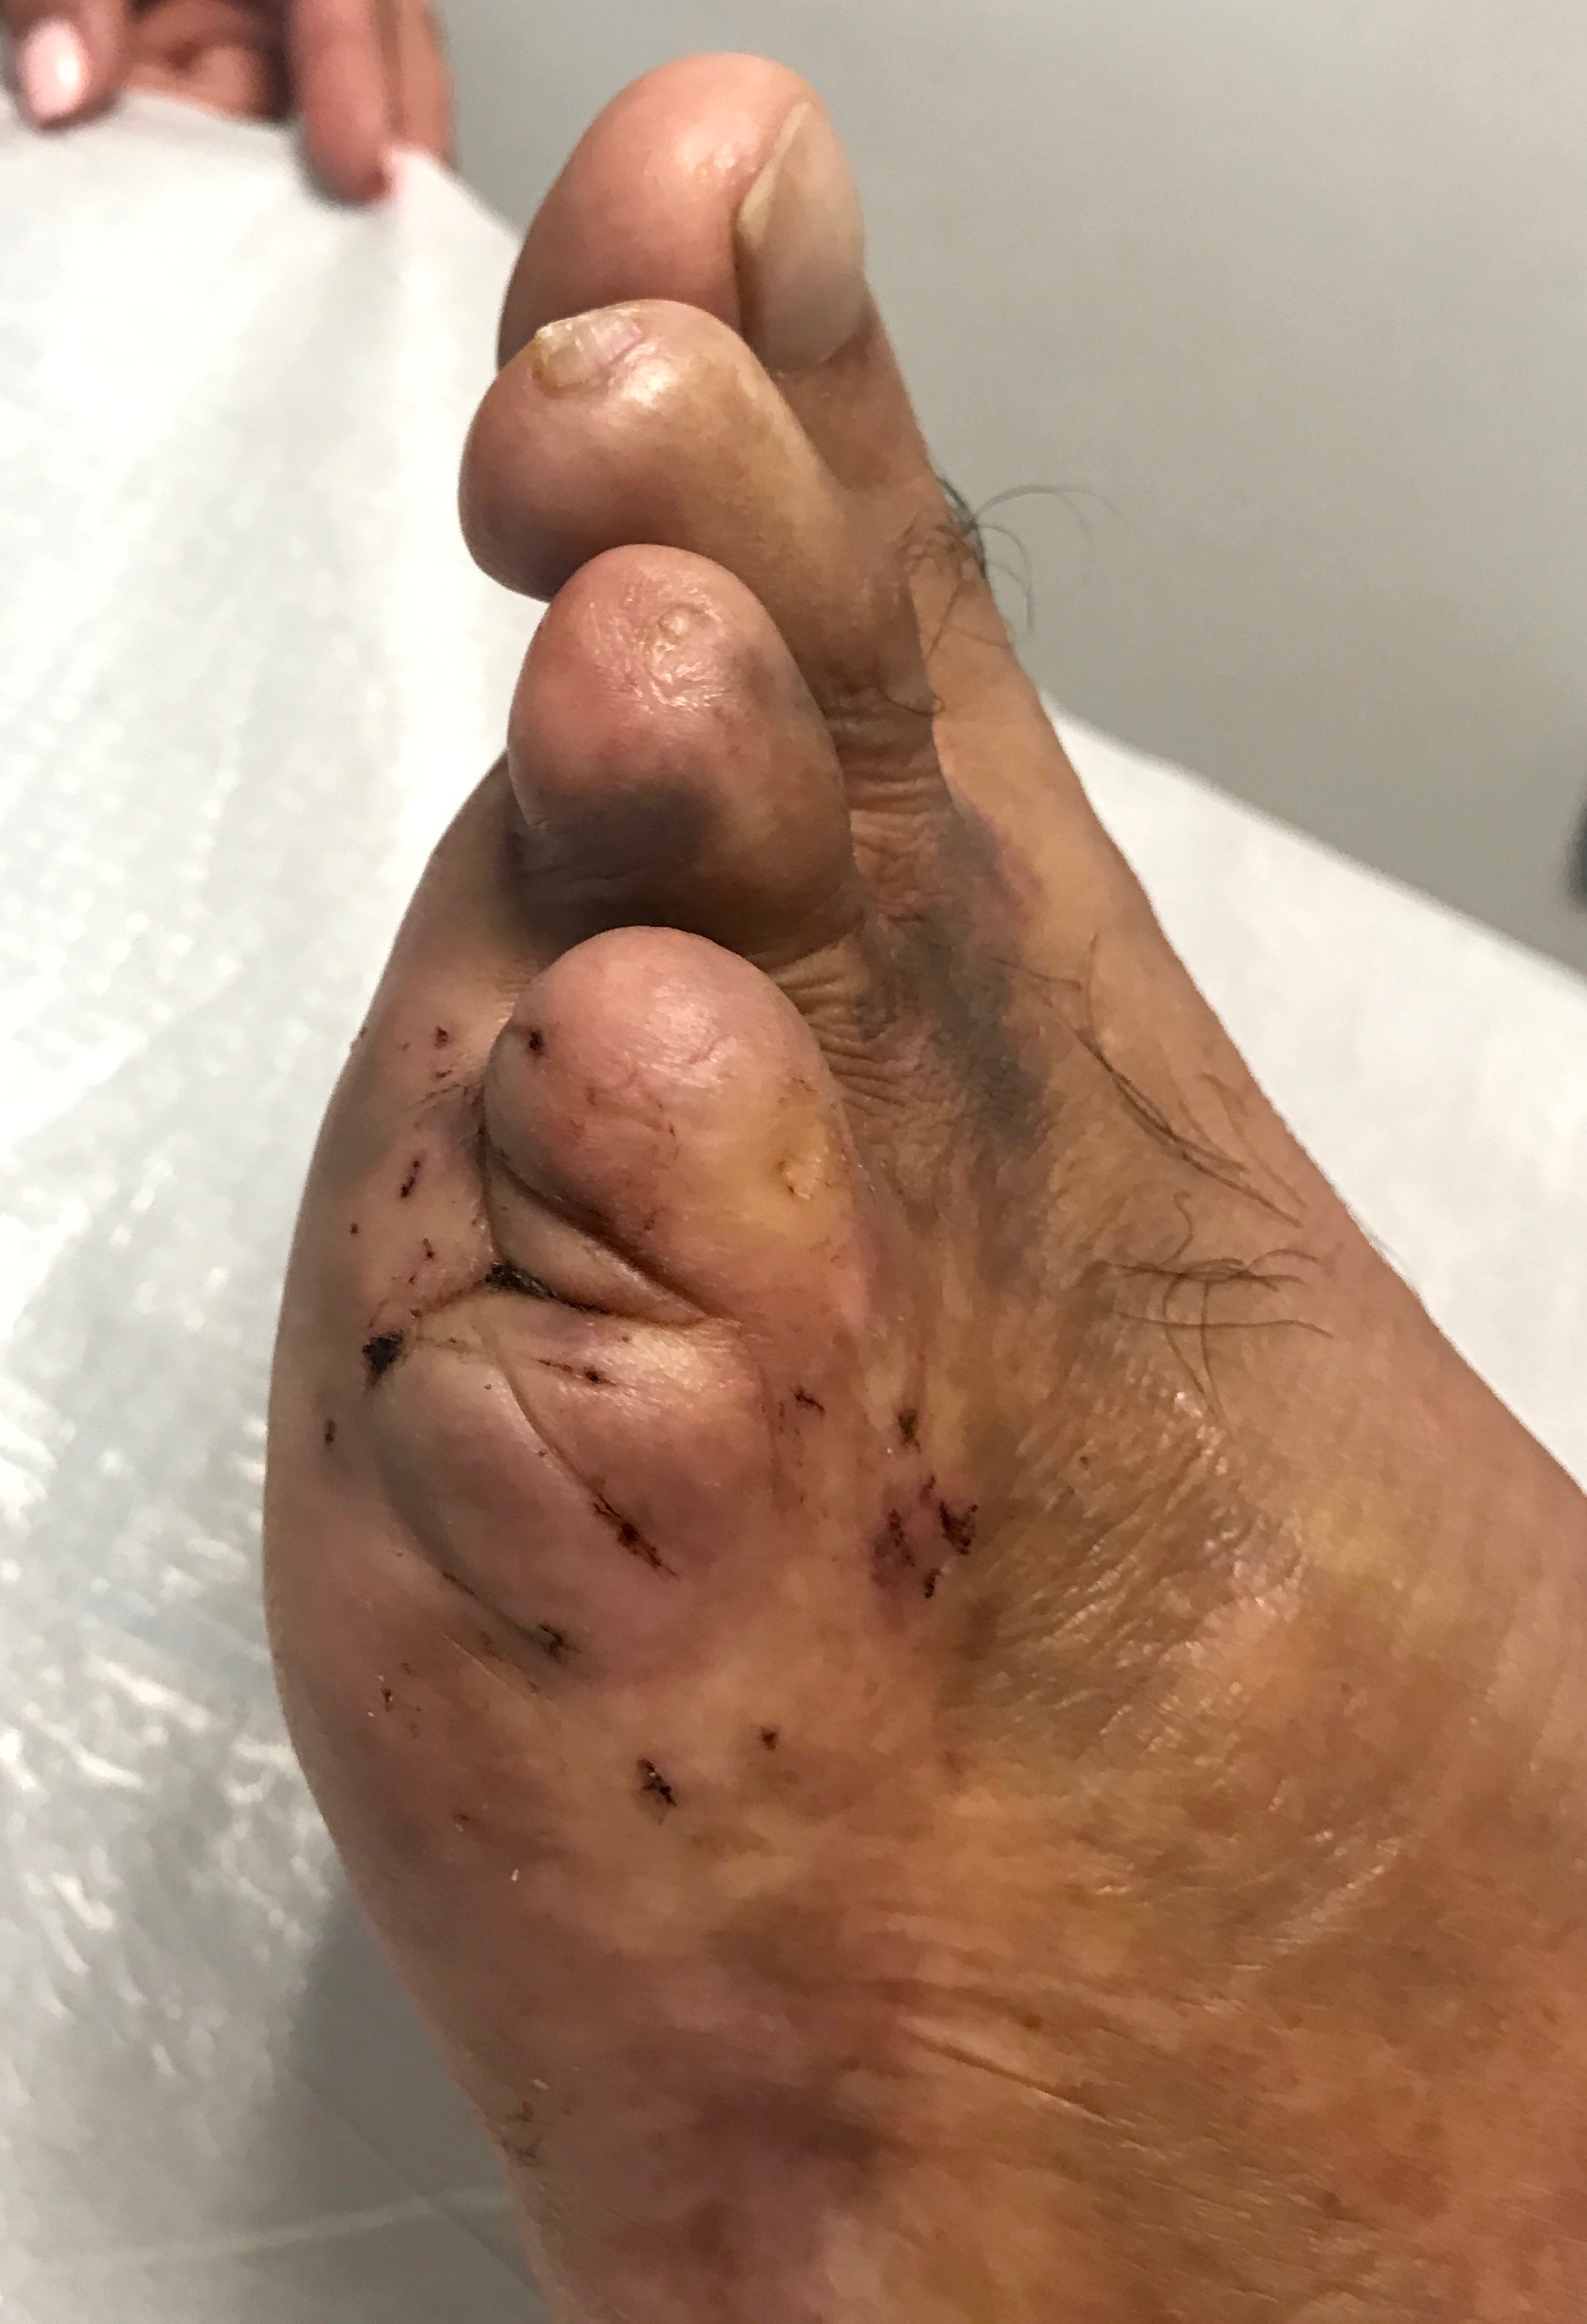

Fotos Clínicas Pre Op.

Dr. Luis Villanueva